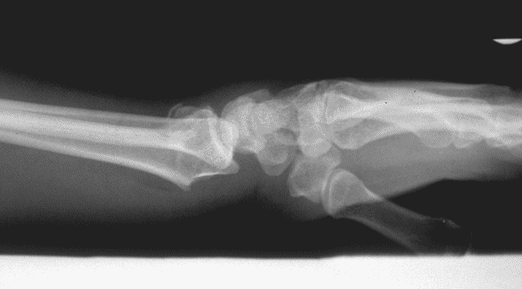

Case 3 Preop

Case3 Preop